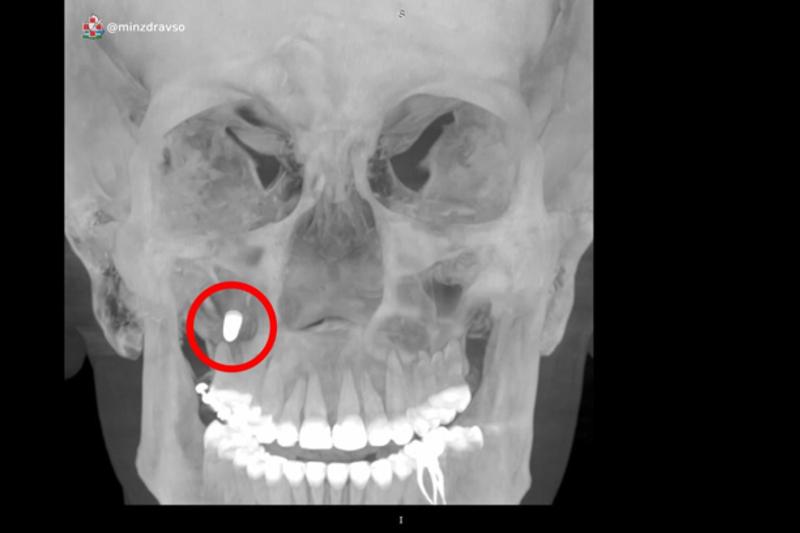

Специалисты медицинского центра «Бонум» извлекли металлический имплант из верхних отделов гайморовых пазух женщины. Его устанавливали несколько месяцев назад в стоматологической поликлинике, но во время процедуры протолкнули в правую верхнечелюстную пазуху. У пациентки появились периодические боли и дискомфорт справа от носа, женщина обратилась к врачу.

Выяснилось, что решить проблему без хирургического вмешательства невозможно. Если бы имплант не был удален, это могло бы привести к серьезному воспалению, усилению боли и кровотечениям. Врачи успешно провели эндоскопическое удаление импланта. Операция была проведена не через разрез за губой, как обычно, а через полость носа, без разрезов и дефектов передней стенки пазухи.